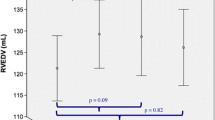

The median follow-up time after anthracyclines was 399 days (IQR 310–517) and covered a time span from 79 to 700 days. Measurements for RV and LV volumes, wall mass and systolic function are summarized in Fig. 1 and the supplemental online Table 1. The quartile ranges for follow-up time were: (79, 146], (146, 231], (231, 350], and (350, 700] days relative to the initiation of anthracycline therapy, corresponding to median follow-up times of 4, 6, 9, and 16 months, respectively. As described previously2, the LVEF and LV mass-index decreased from baseline, reaching 53.8 ± 8.4% at (231, 350] days (median 9 months) and 36 ± 6 g/m2 at (350, 700] days (median 16 months) after chemotherapy respectively (P < 0.001; Fig. 1A,B).

AB: Baseline and post-anthracycline ejection fraction (LV and RV) and ventricular mass (LV and RV). (A) LV EF (left) was significantly lower during all follow-up periods after anthracycline therapy (P < 0.001); RV EF (right) reached a minimum around (146, 231] days after anthracycline initiation (P = 0.002 vs. pre-DOX), followed by a slight recovery. (B) LV and RV ventricular mass index showed steady incremental decreases over the entire follow-up and in all follow-up periods both LV and RV mass index were significantly (P < 0.001) below their baseline averages (+P < 0.1; *P < 0.05; **P < 0.01; ***P < 0.001).

The RV end-diastolic volume index did not change after anthracyclines (supplemental online Table 1). In contrast, there was an approximately 25% increase in the RV end-systolic volume index from 20.4 ± 6 ml/m2 at baseline to 25.2 ± 10 ml/m2 at (146, 231] days after anthracycline therapy (P < 0.011). This increase in the RV end-systolic volume occurred with a parallel decline in the RVEF from 55.6 ± 9% to a minimum of 46.3 ± 6.8% at (231, 350] days after anthracyclines (P < 0.001 compared with baseline, Fig. 1A). The RV mass index decreased by 28% after anthracyclines, from 18.2 ± 4 g/m2 at baseline to 13 ± 2.8 g/m2 at a median of 16 months after chemotherapy (P < 0.001 compared with baseline, Fig. 1B), similar to a parallel 30% decrease of LV mass index. The RVEF correlated only weakly (repeated measures correlation coefficient r = 0.23, P = 0.05; CI [− 0.012, − 0.44] with the LVEF.

After anthracycline therapy, 15 (58%) patients showed signs of LV systolic dysfunction (LVEF < 55%; mean decrease of LVEF in group developing LV dysfunction: 18.5 ± 5.3%; min. change 11.5%) on one of the follow-up CMR examinations, i.e. these patients met criteria for LV cardiotoxicity, namely a > 10% reduction in LVEF from baseline to < 55%, in the absence of heart failure symptoms. Patients with LV systolic dysfunction at follow-up had a lower RVEF at baseline (51.49 ± 7.72 vs. 60.82 ± 8.91%; P = 0.011) and a higher RV ESVi (23.66 ± 6.15 vs. 17.20 ± 4.07 ml/m2; P = 0.005). Patients with an RV ESVi above its median at baseline, had an overall lower LVEF at multiple time points after anthracyclines (P < 0.001), though at baseline LVEF was > 60% in all patients (Fig. 4A). In patients with RV ESVi ≥ median at baseline, LV systolic dysfunction was more likely after anthracyclines (P = 0.0028 for effect of RV ESVi ≥ median at baseline, Fig. 4B). Similarly, patients with an RVEF below its median at baseline, had an overall lower LVEF at multiple time points after anthracyclines (P < 0.001).

Predictors of LV systolic dysfunction post-anthracycline: (A) LVEF was within the normal range in all patients at baseline and declined significantly after anthracycline therapy (P < 0.001). After anthracyclines, LVEF was significantly lower in patients with higher than median RV ESVi at baseline compared to in patients with an RV ESV index < its median (55%) at baseline (BL). The solid lines represent cubic regression splines for the time from anthracycline therapy initiation, which were estimated with a generalized additive model (GAM) with mixed effects. The model also included RV ESVi at baseline as independent predictor. The effect of an above median RV ESVi at baseline remained significant (P < 0.001) when LV ESVi at baseline was added to the model. (B) The bar graph presents an analysis complementary to A for the proportion of patients with LVEF < 55% during follow-up periods. LV EF < 55% was significantly more frequent during follow-up if RV ESV index ≥ median at baseline—the final follow-up period from > 350 to 700 days, the proportion reached 75% percent. At baseline, all patients with RV ESVi < median had an LVEF within the normal range. The error bars denote the 95% confidence intervals and were generated by the bootstrap method with sampling by patient identifier.